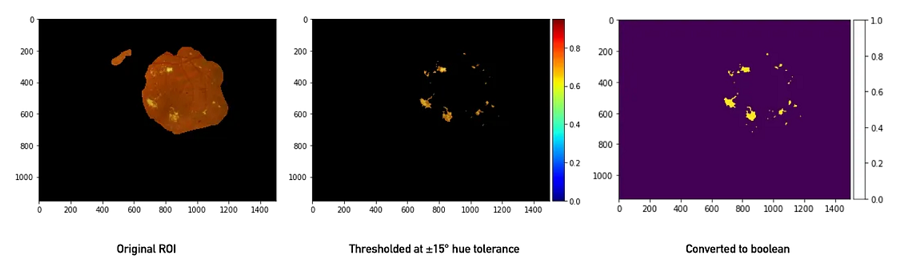

我们从一些图像处理开始,即细化感兴趣的区域。每张图像都由四位专家标记,从而创建了一个蒙版。我们可以对蒙版进行阈值处理,以要求一定数量的专家达成共识,这是带注释的研究图像中广泛使用的技巧(如果您不熟悉它,请滚动到底部!)。然后,我们使用硬性渗出液相对突出的亮黄色将它们转换为 GNG 可以开始表征的数据点(有关细节,请参阅配套笔记本,其中解释了一些额外的技巧,包括一些形态变换)。

接下来,我们利用脂质渗出液具有非常可识别的黄色这一事实,通过使用 OpenCV 的 inRange 函数对其进行阈值处理。此时,我们上面执行的 ROI 蒙版派上了用场,因为视神经盘(血管进入的亮黄色圆形结构,神经节神经元的轴突离开视网膜加入视神经)通常具有相似的颜色,具体取决于照明。使用 inRange 时,通常将图像转换为 HSV(色调、饱和度和明度)格式,因为这样可以更轻松地指定特定色调范围内的颜色。在 HSV 中,色调(“颜色”)占据颜色向量的单个元素(通常指定为色环上的度数),因此指定所有黄色就像指定黄色的近似色调角(大约 60°)并排除低饱和度(浅色,趋向于白色)或低明度(深色,趋向于黑色)边缘一样简单。对于 RGB 中的大多数颜色,这会复杂得多!幸运的是,OpenCV 及其 Python 绑定具有出色的颜色空间转换功能。

使用 OpenCV 的颜色阈值功能从原始 ROI 中提取硬脂质渗出物。只有落在特定色调角度范围内的值才会被保留。经过一些形态学操作以消除噪音后,我们留下了一个布尔图像,该图像将转换为二进制网格格式,以供 GNG 进行训练。